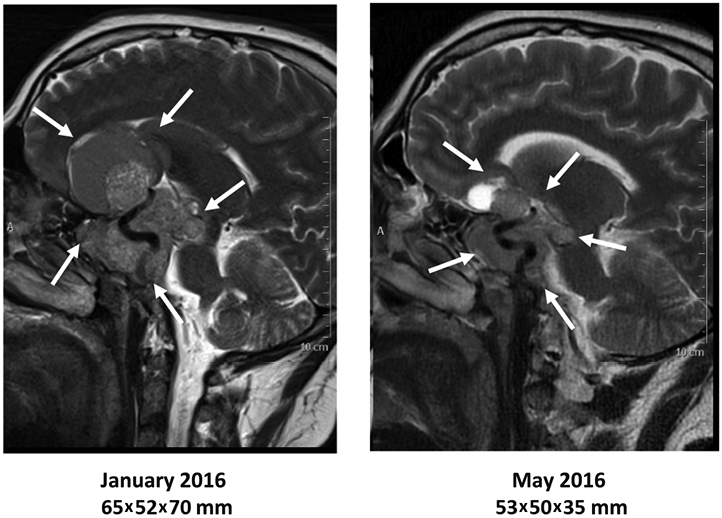

Спустя 6 мес после инициации терапии агонистами дофамина пациент отметил регресс головной боли, значительное улучшение общего самочувствия. По данным МРТ головного мозга имела место положительная динамика в виде уменьшения размеров образования до 53×50×35 мм (рис. 2) на 25% в максимальном размере.

Рис. 2. Изменение размеров образования гипофиза через 6 мес. терапии каберголином.